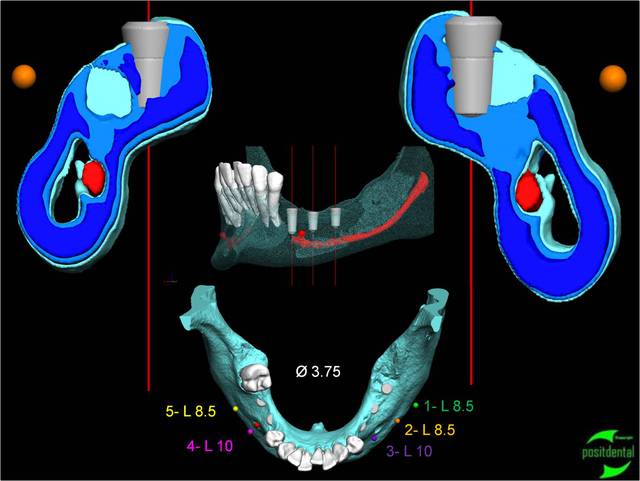

en vue indirecte

Image4 lajbqk - Eugenol

2010.04.positdental - Eugenol